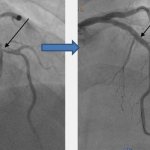

Результат лечения